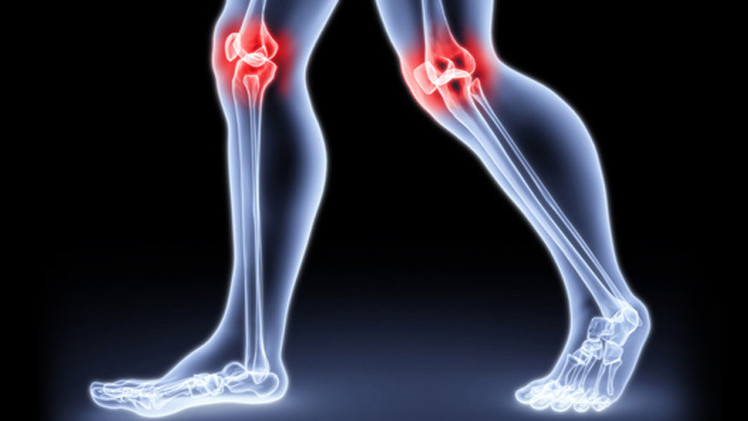

هذا المرض غير قابل للعلاج حاليا، لذلك فهو الأكثر انتشارا في العالم، وسببه تآكل الغضاريف التي تساعد المفاصل في تحمل الأثقال الناتجة عند الحركة.

حاليا لا يوجد أي اختبار خاص لتشخيص الإصابة بهذا المرض، لذلك لا يمكن تشخيص المرض إلا بعد ان يصل الى مرحلة متقدمة جدا. العلاج الوحيد في هذه الحالة يكون عملية جراحية لتبديل الغضروف.